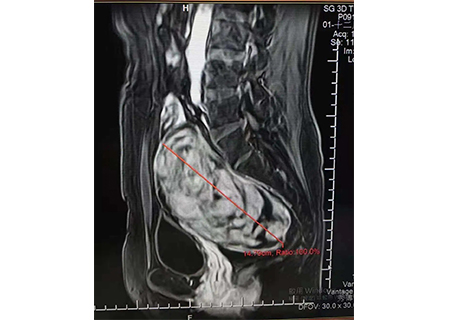

消融坏死前14公分

消融坏死对比图如上↑

治疗后一周追踪,肌瘤已经从14公分降为11公分,患者的盆腔压迫感也减轻很多。